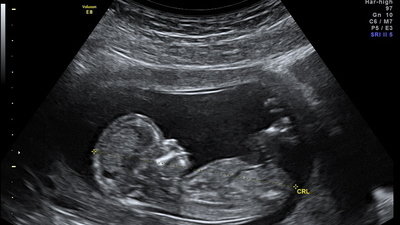

Ultrasound is used routinely for fetal imaging worldwide and its safety is hotly debated. Many studies have demonstrated that excessive ultrasound exposure can cause changes in cognition, sociability, and physical development in animal models. Studies from China corroborate that excessive prenatal ultrasound may cause harm to humans. Until more research is performed the safety of prenatal ultrasonography is questionable. We must raise awareness and demand more studies be funded.

(1) Sonographers do not typically record how much ultrasound is used during a scan session. This makes it impossible for researchers to correlate ultrasound dose with health outcomes. We do not know for sure whether ultrasound is actually safe or could be linked to risks. There are stark correlations between groups that typically receive a higher number of ultrasounds and a greater emergence of health conditions, such as autism. Unfortunately, because there is no dose response to study, relevant epidemiology is untenable. [Relevant citations: FetalUltrasoundSafety, the website of Dr. David Toms - a practicing radiologist; www.ultrasound-autism.org -- an independent site tracking known ultrasound side effects research]

(2) Nearly half of all medical ultrasound units in clinical circulation are defective. A defective unit may have a worse picture, requiring extra exposure in order to make a diagnosis. More frequent maintenance of ultrasound units would not only be prudent for safety, it would also promote engineering and tech jobs which could help the ailing economy. [Relevant citations: High incidence of defective equipment in circulation, Annual calibration is not sufficient]

(3) The average number of ultrasounds for a healthy pregnancy is 4, while high-risk pregnancies can receive upwards of 20 or more. The skill of individual sonographers varies greatly, and so does how much ultrasound they use. Some clinics offer hour long ultrasound recordings for keepsake and vanity. These practices disregard safety regulations and are allowed to continue; educating the public is likely the only way to solve this problem. [Relevant citations: Proliferation of Fetal Ultrasonography, Ultrasound is safe, right?, Clinical end users show poor understanding of ultrasound safety]